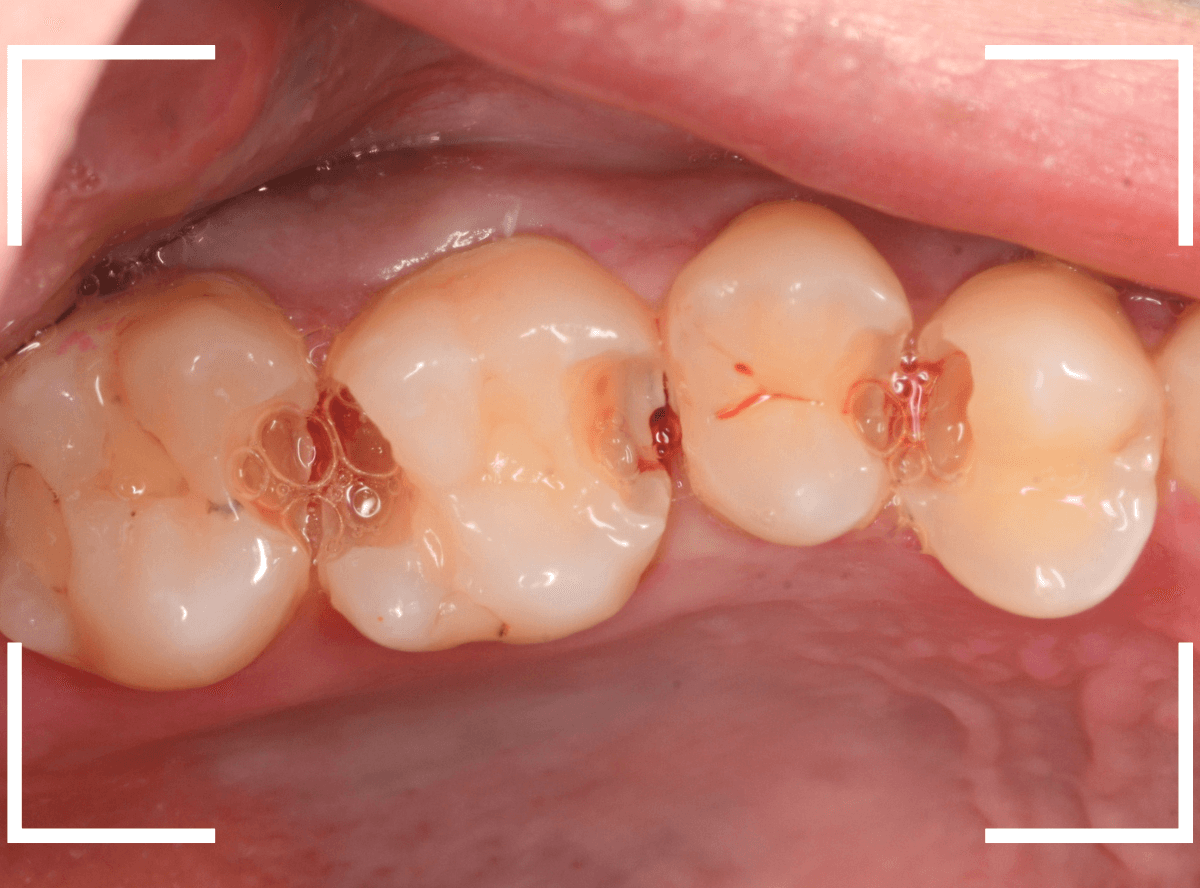

Case.23 歯のすきまから両側が大きな虫歯

「下の奥歯が痛む」という訴えで来院された患者さんのケースです。

目視でも、手前の奥歯がかけていて、中で虫歯が広がってるであろうことは予想できます。

ピンセットで歯を叩いてみても、手前の奥歯が痛むようです。

レントゲン写真で確認します。

青い線が神経、赤い線が虫歯の範囲です。

奥歯の方がより深い虫歯に見えますが、再度打診で確認したところ、やはり手前の奥歯が痛むそうです。